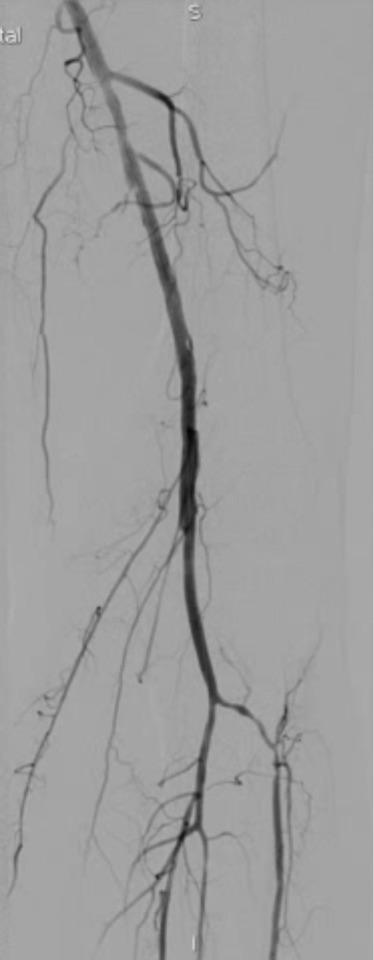

下面是术中dsa造影血管堵塞的情况

最后的结果令人满意,而且达到了患者的诉求,尽量不植入支架,来看看最后的造影结果吧